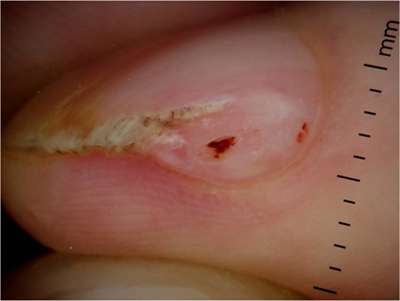

Onychopapillome (figure 1)Parmi les diagnostics différentiels de l’onychopapillome il faut désormais compter :– l’acanthome du lit [1] (ou nommé également kératose séborrhéique) avec des présentations variables : mélanonychie avec hyperkératose du bord libre, grains de milium, xanthonychie, leuconychie ou érythronychie plus rares. La figure ci-dessous monte le cas d’un patient de 54 ans. Le diagnostic différentiel principal dans ce cas reste la maladie de Bowen.– l’onychopapillome malin, publié par [...]